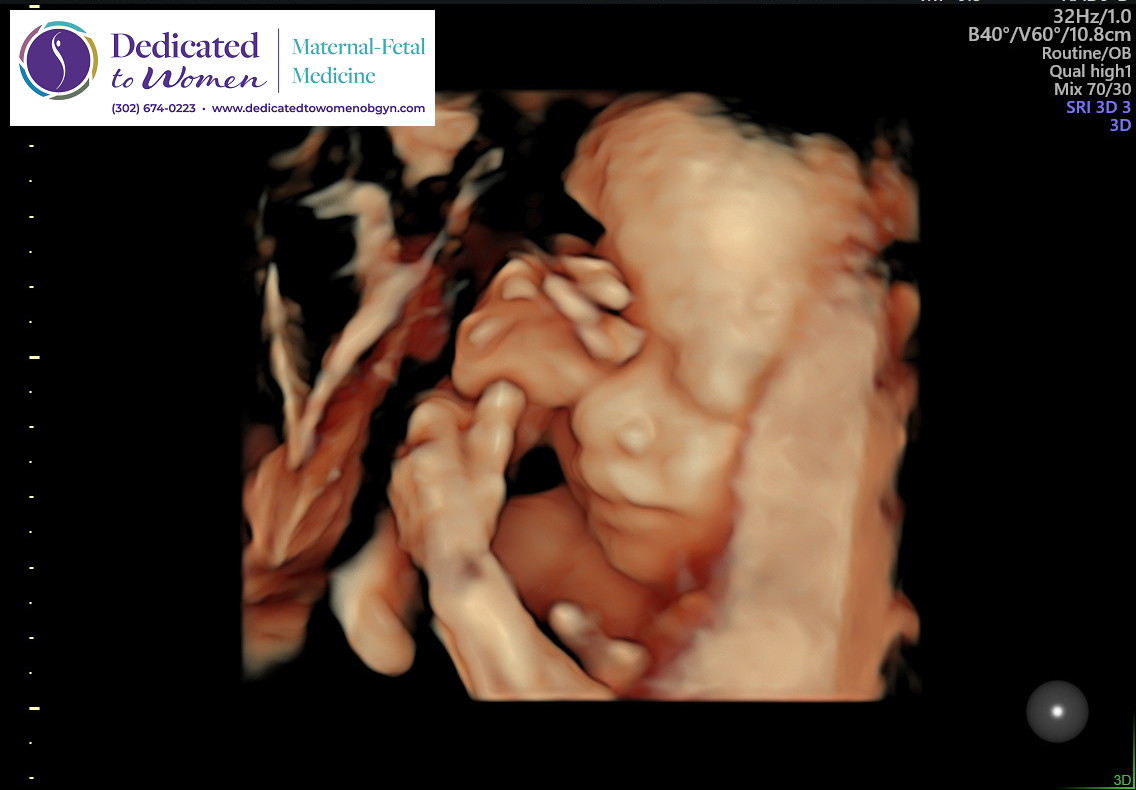

So fast forward to today. We are expecting a baby boy. I have PCOS, I didn't even know getting pregnant was a possibility for me as I was previously told it was borderline impossible.. that I was as good as infertile.

Now, Ive heard it all already. "How irresponsible of you" "Abort the baby" "Adoption" "You did this to yourself". I've heard all of it I promise you. Trust and believe I considered it all, because I too thought... how dare I? How dare I bring a baby into a situation like this. But our situation is not at all as bad as it really could. Amias will be born to 2 loving parents, 2 working parents (i'm currently on paid medical leave due to my pregnancy being very high risk). Our finances are the ONLY thing in the way of blossoming fully for this baby. It's expensive to be houseless. But I have hope, and I want my son. I want my son to have everything I didn't, and to never feel what I or his father felt growing up.